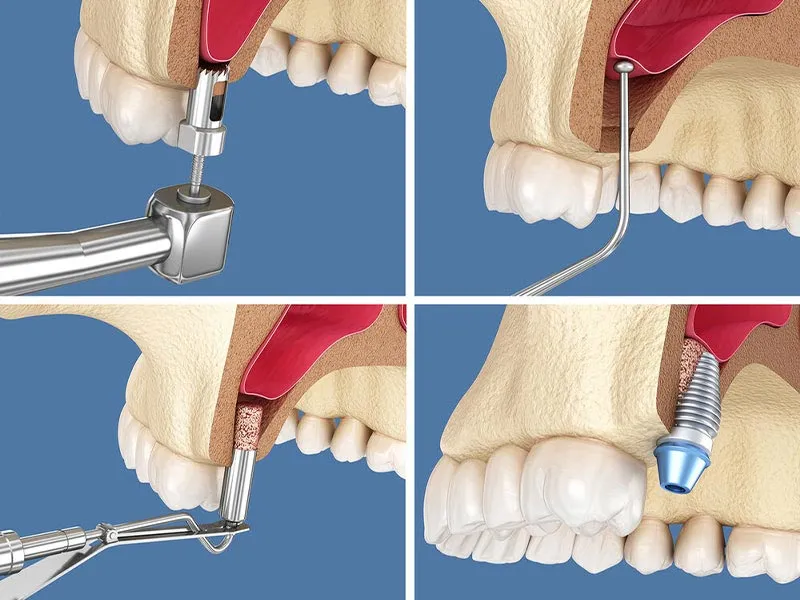

امروز دندانپزشکان به صورت گسترده از روش سینوس لیفت باز استفاده می کنند. به منظور انجام جراحی سینوس لیفت باز به استخوان با اندازه 5 سانتی متر احتیاج دارید. در روش سینوس لیفت باز، برش روی باف لثه ایجاد شده و بعد سینوس به بالا حرکت داده می شود.

پس از طی کردن این مرحله، قسمت خالی از طریق مواد پیوندی و پودر استخوان کامل و پر می شود. جراح باید به منظور انجام عمل سینوس لیفت باز تبحر زیادی داشته باشد. پس جهت انجام این عمل جراحی به هر مرکز دندانپزشکی مراجعه نکنید.

در طی این جراحی

| 1 | قسمتی از لثه در بخش جانبی فک بالا بریده شده و روی استخوان سوراخی ایجاد می شود |

| 2 | سپس، از طریق این سوراخ، دندانپزشک مخاطی را پیدا می کند که سینوس داخل آن را می پوشاند |

به این غشاء، اشنایدر هم می گویند.

سپس

| 3 | دندانپزشک می تواند با ابزارهای مخصوص جراحی و با رعایت احتیاط بدون آسیب به غشاء، مخاط سینوس را بلند کرده و مواد استخوانی را در آنجا می ریزد |

| 4 | بعد از اینکه عمل لیفت سینوس باز تمام شد، زخم ها بخیه زده می شوند |

به منظور تشکیل بافت استخوانی به صورت کامل باید بازه زمانی 4 تا 6 ماه منتظر ماند. پس از گذشت این بازه زمانی دندانپزشک می توانند اقدام به نصب ایمپلنت کند.